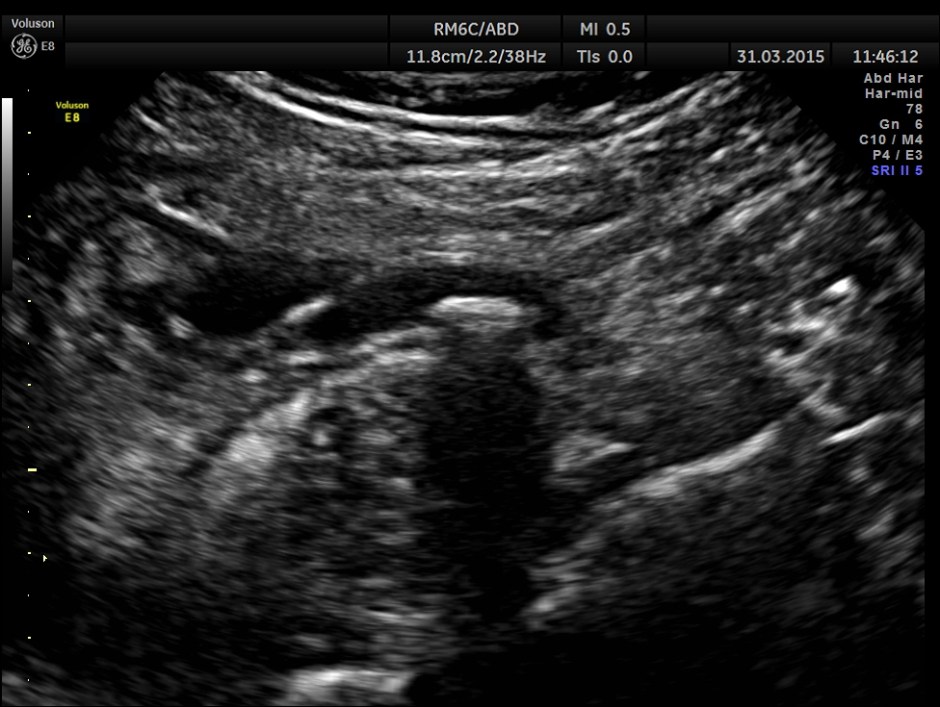

Ultrasound showed the following.

Scan ( with a regular abdominal probe ) over RIF shows an echogenic object with posterior acoustic shadowing within a dilated ” tube ” .

Can we jump to the diagnosis of ureteric calculus now ?

Is there an incongruity between the size of the calculus and the ” ureteric dilatation ” and the pelvi calyceal dilatation ?

Now this looks more like an inflamed appendix with a prominent fecolith of size 11.4 mms , throwing a shadow.